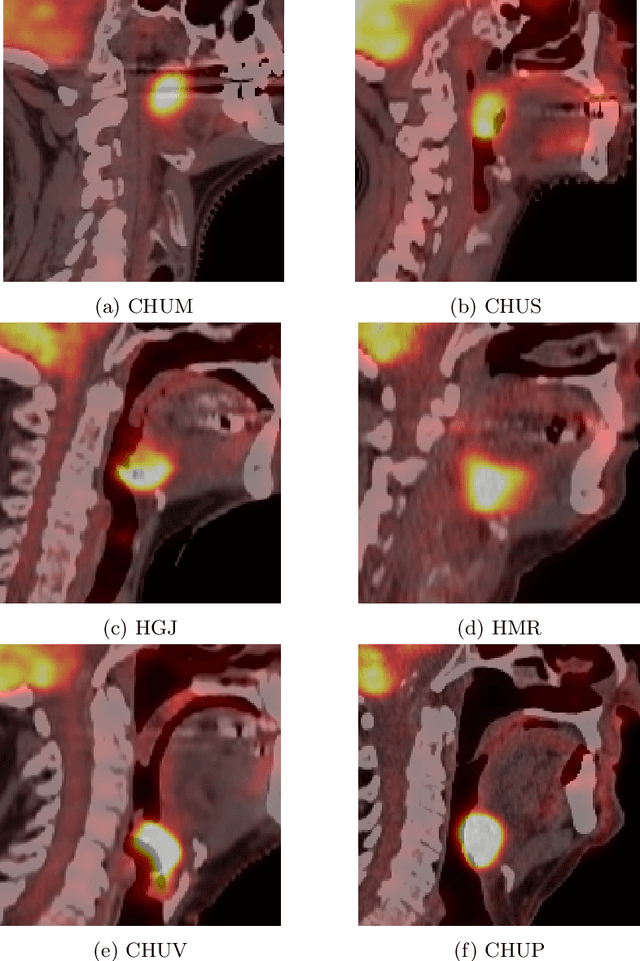

Abstract:This paper presents an overview of the second edition of the HEad and neCK TumOR (HECKTOR) challenge, organized as a satellite event of the 24th International Conference on Medical Image Computing and Computer Assisted Intervention (MICCAI) 2021. The challenge is composed of three tasks related to the automatic analysis of PET/CT images for patients with Head and Neck cancer (H&N), focusing on the oropharynx region. Task 1 is the automatic segmentation of H&N primary Gross Tumor Volume (GTVt) in FDG-PET/CT images. Task 2 is the automatic prediction of Progression Free Survival (PFS) from the same FDG-PET/CT. Finally, Task 3 is the same as Task 2 with ground truth GTVt annotations provided to the participants. The data were collected from six centers for a total of 325 images, split into 224 training and 101 testing cases. The interest in the challenge was highlighted by the important participation with 103 registered teams and 448 result submissions. The best methods obtained a Dice Similarity Coefficient (DSC) of 0.7591 in the first task, and a Concordance index (C-index) of 0.7196 and 0.6978 in Tasks 2 and 3, respectively. In all tasks, simplicity of the approach was found to be key to ensure generalization performance. The comparison of the PFS prediction performance in Tasks 2 and 3 suggests that providing the GTVt contour was not crucial to achieve best results, which indicates that fully automatic methods can be used. This potentially obviates the need for GTVt contouring, opening avenues for reproducible and large scale radiomics studies including thousands potential subjects.

Abstract:Quantitative extraction of high-dimensional mineable data from medical images is a process known as radiomics. Radiomics is foreseen as an essential prognostic tool for cancer risk assessment and the quantification of intratumoural heterogeneity. In this work, 1615 radiomic features (quantifying tumour image intensity, shape, texture) extracted from pre-treatment FDG-PET and CT images of 300 patients from four different cohorts were analyzed for the risk assessment of locoregional recurrences (LR) and distant metastases (DM) in head-and-neck cancer. Prediction models combining radiomic and clinical variables were constructed via random forests and imbalance-adjustment strategies using two of the four cohorts. Independent validation of the prediction and prognostic performance of the models was carried out on the other two cohorts (LR: AUC = 0.69 and CI = 0.67; DM: AUC = 0.86 and CI = 0.88). Furthermore, the results obtained via Kaplan-Meier analysis demonstrated the potential of radiomics for assessing the risk of specific tumour outcomes using multiple stratification groups. This could have important clinical impact, notably by allowing for a better personalization of chemo-radiation treatments for head-and-neck cancer patients from different risk groups.